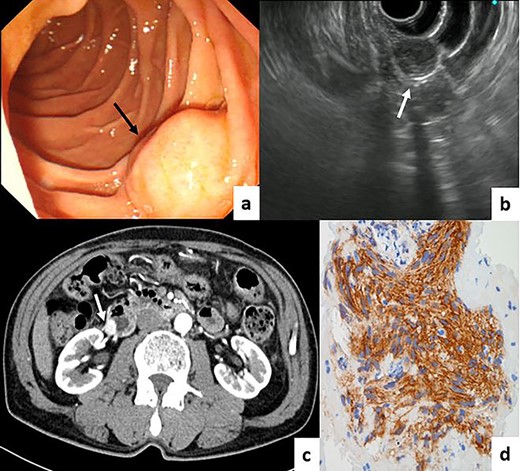

A 72-year-old man was found to have a duodenal tumor on complete medical examination. Esophagogastroduodenoscopy (EGD) showed a submucosal-like mass (1.5 × 1.5 cm) on the opposite side of the duodenal papilla (Fig. 1a). Endoscopic ultrasound (EUS) revealed a tumor derived from the muscular layer of the duodenal wall (Fig. 1b). Computed tomography (CT) showed an enhanced tumor (1.5 × 1.7 cm) in the descending part of the duodenum without lymph node metastasis or distant metastasis (Fig. 1c). The pathological diagnosis of the fine needle aspiration biopsy samples was a gastrointestinal stromal tumor (GIST) (Fig. 1d). We performed partial duodenectomy and pedicled jejunal flap reconstruction for a 6 × 8 cm duodenal defect (Fig. 2a). A part of the jejunum at a distance of 30–40 cm from the ligament of Treitz was isolated and formed into a pedicled flap to fit the duodenal defect (Fig. 2b). The jejunal flap was passed through the retro-colic route, and duodenojejunal anastomosis was performed using an Albert–Lembert suture (Fig. 2c and d). In addition to the jejunojejunal anastomosis, we closed the space between the mesentery of the colon and jejunal flap. The pathological diagnosis of the resected specimen was the same as that of the preoperative diagnosis. The patient was discharged on the 11th postoperative day without any surgical complications. No tumor recurrence or gastrointestinal symptoms were reported 13 months after surgery.

(a) EGD showed a submucosal-like mass on the opposite side of the duodenal papilla (black arrow). (b) EUS revealed a tumor derived from the muscular layer of the duodenal wall (white arrow). (c) CT showing an enhanced tumor in the descending part of the duodenum. (d) Immunohistochemical assessment of the fine needle aspiration biopsy samples showing the GIST (KIT ×400).